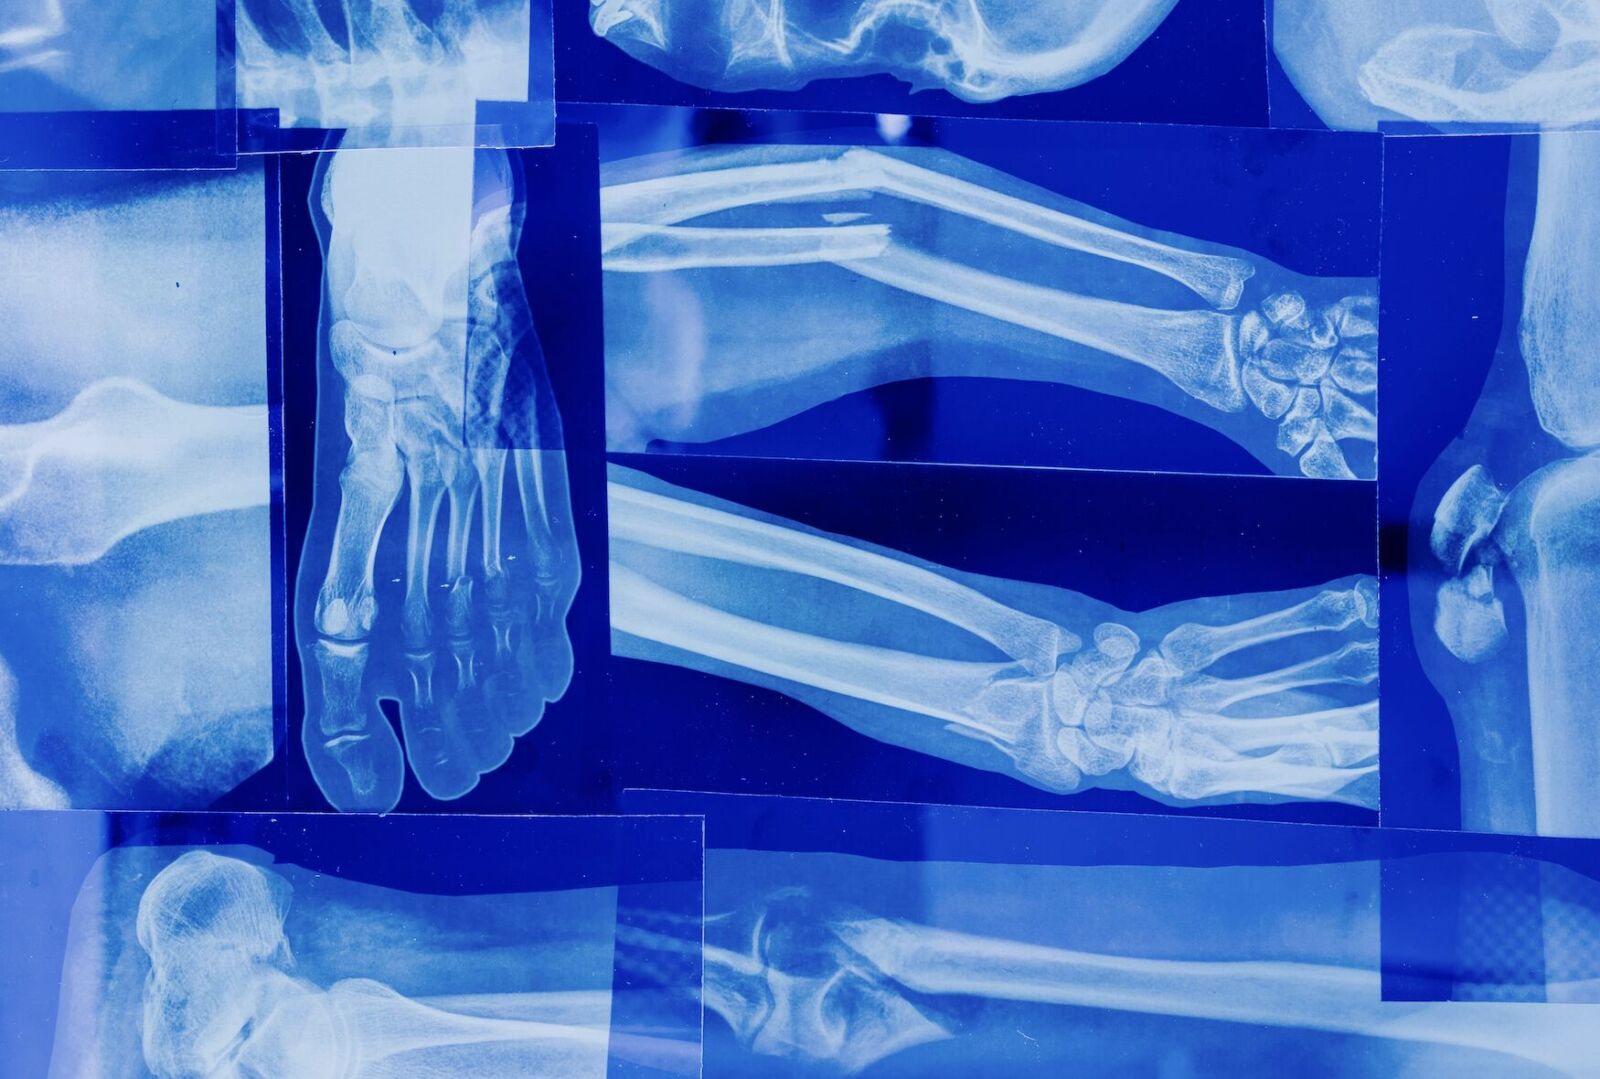

照片來源:示意照/翻攝自Pexels